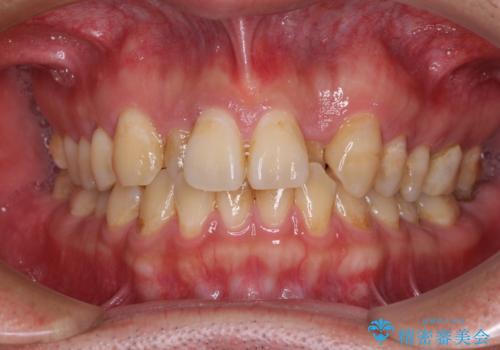

- 虫歯が多く、セラミッククラウンにより虫歯治療を行っている途中で矯正治療をしたいとのことで来院された患者様です。

上顎前歯が舌側に転位しており、なるべく早く楽に矯正したいとのことで、ワイヤー矯正を行うこととしました。